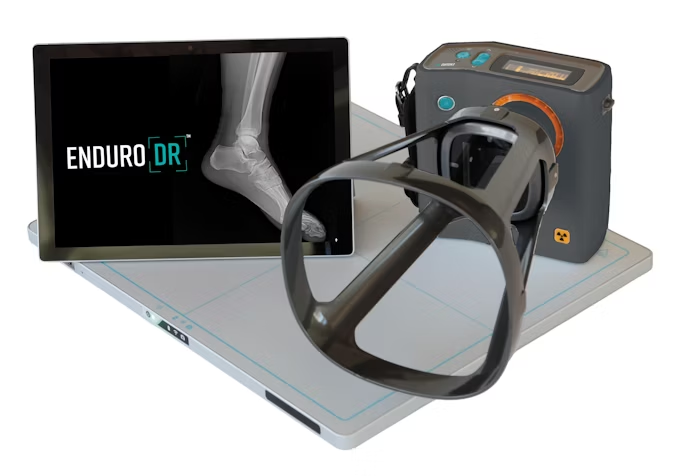

Whether physicians are using the SMART-C® and tablet at the point-of-care or mounted on the support stand in a medical room, they have the flexibility to acquire sharp motion images at the exact angle needed, to properly treat their athletes. By facilitating prompt and precise assessment of bone fractures, dislocations, stress fractures, wrist and hand injuries, and ankle fractures, the SMART-C® significantly enhances the management and recovery of sports-related injuries.